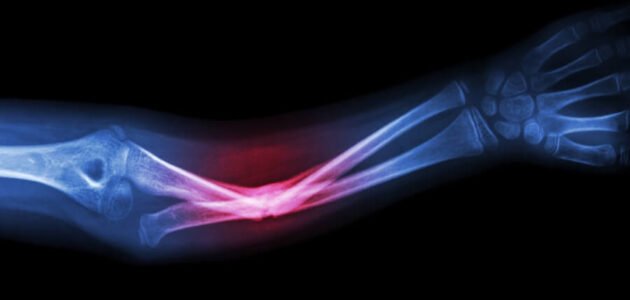

لماذا تلتئم العظام المكسورة ؟، قد يتعرض العديد من البشر للإصابة بكسور العظام، والعظام المكسورة لديها قدرة مذهلة على الشفاء، خاصة عند الأطفال، حيث تتشكل عظام جديدة في غضون بضعة أسابيع من الإصابة، على الرغم من أن الشفاء الكامل قد يستغرق وقتا أطول، فقد تحتاج أحيانا بعض العظام المكسورة الى التدخل الجراحي في كان هناك تهشم للعظام الداخلية، حيث يجب حينها التوجه الى طبيب لتلقى العلاج المناسب.

لماذا تلتئم العظام المكسورة